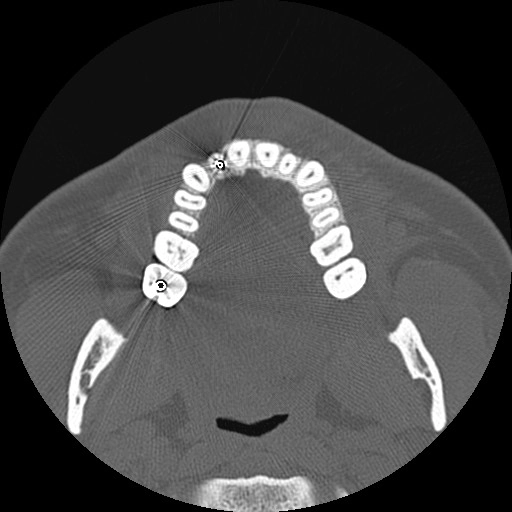

CT ống tai